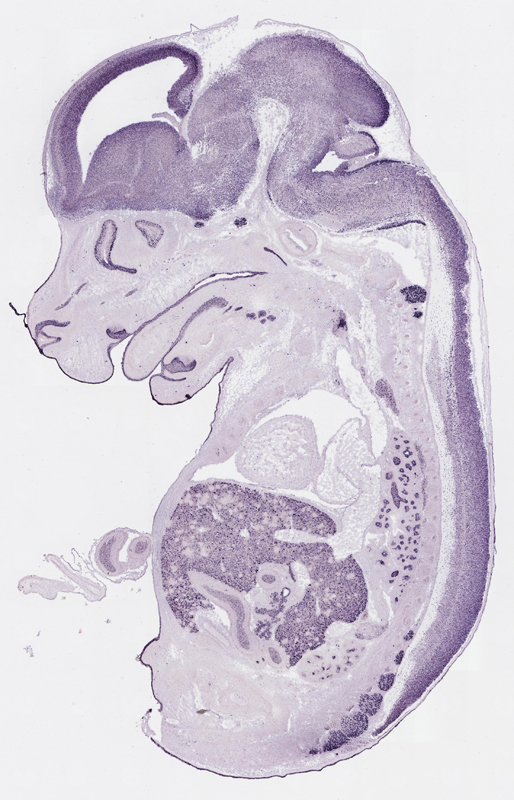

Specimen

euxassay_003287_04:

embryonic day 14.5